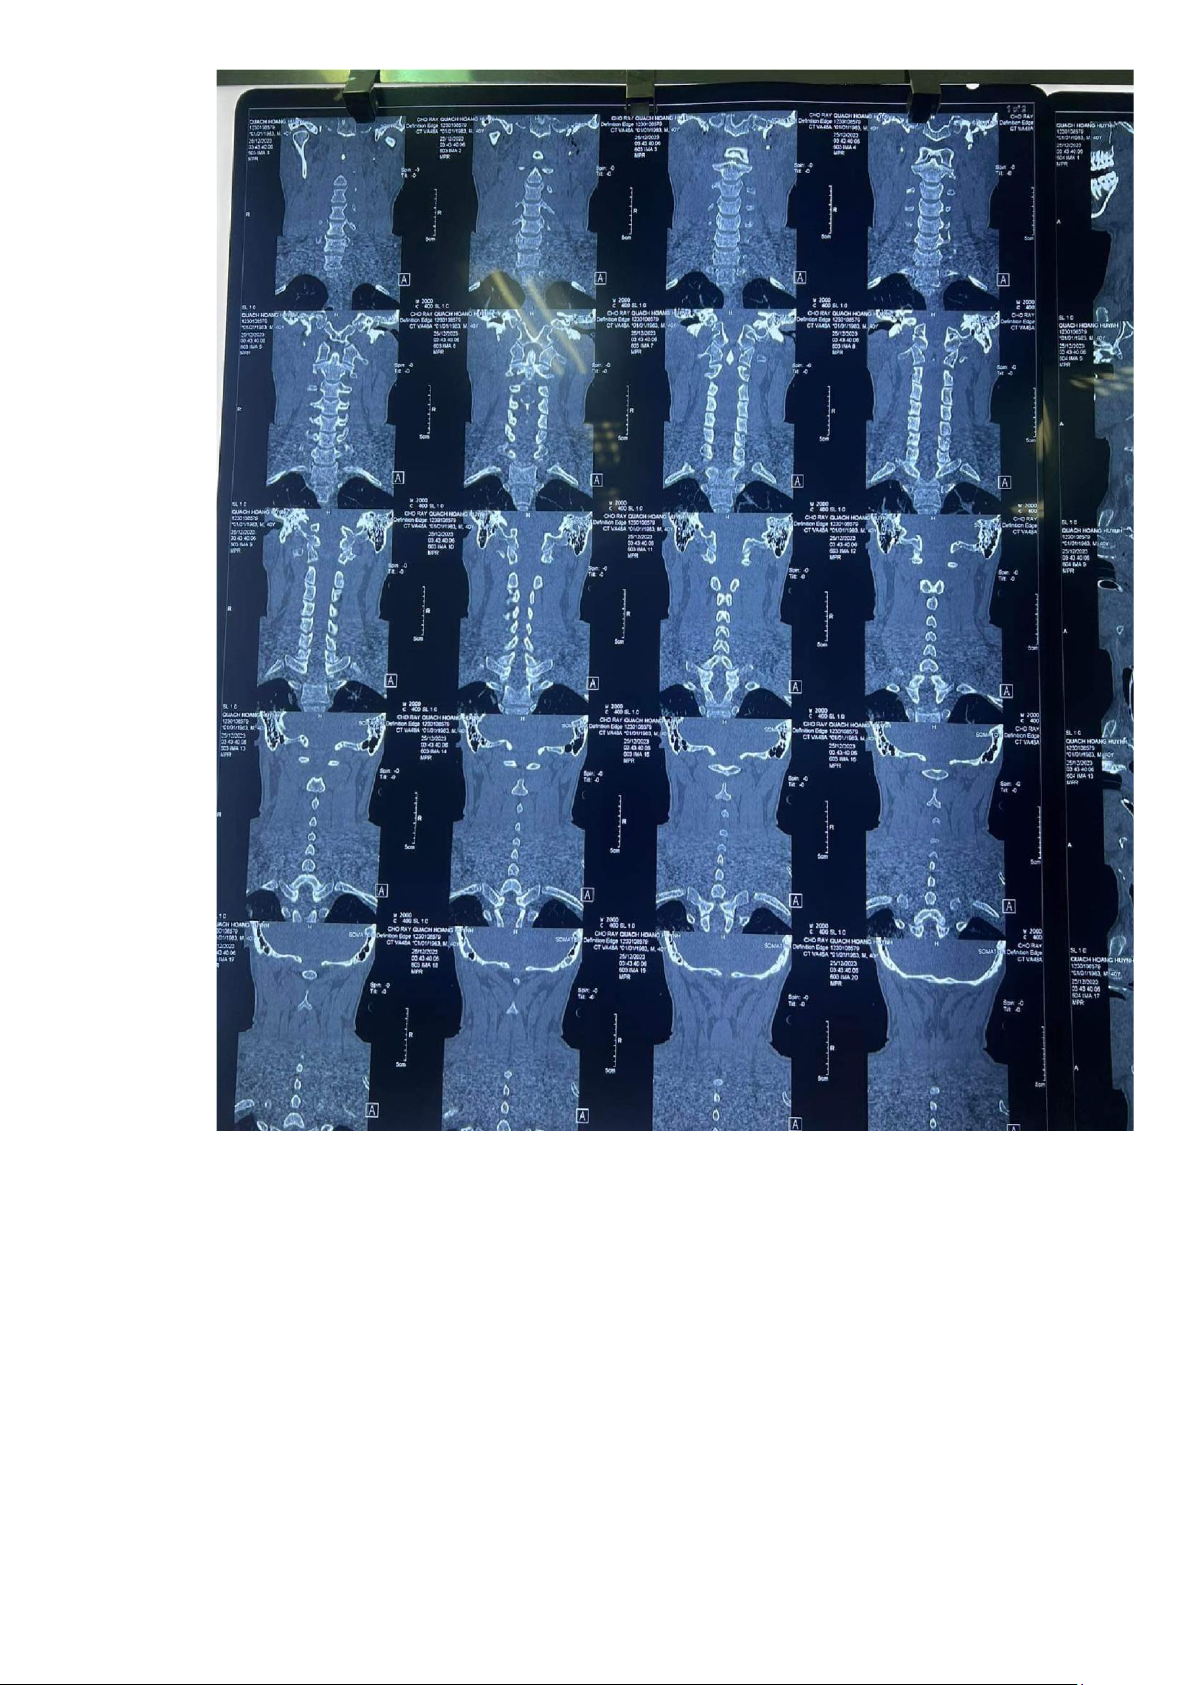

7. CT scans cột sống cổ không cản quang 25/12/2023 lOMoAR cPSD| 45469857 lOMoAR cPSD| 45469857 lOMoAR cPSD| 45469857

- Không gãy xẹp thân sống, không trượt cột sống cổ

- Gãy mõm ngang bên (T) C6 tụ dịch vùng hầu họng